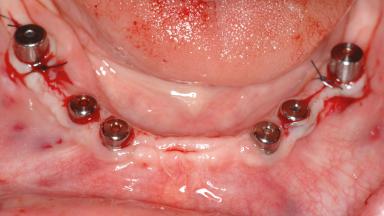

Le Fort I Interpositional Graft and Mandibular Sandwich Osteotomy for Maxillofacial Rehabilitation after Severe Periodontitis

# of Implants 14

Type of Implants Two-Piece

Bone Augmentation Horizontal|Sinus Floor Elevation|Staged|Vertical